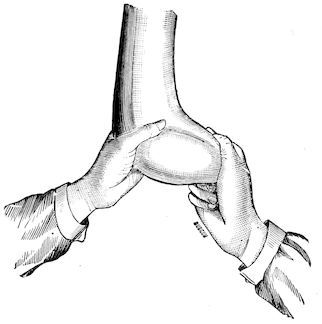

Fig. 3.—Pig suffering from osseous cachexia (fourth stage).

114. The fourth phase, or period of osteomalacia, i.e. softening of the bones, is also the last. It is rarely seen in large animals like horses and oxen, because accidents so often accompany the preceding stages and necessitate slaughter; but it is common in goats and pigs.

In this phase the bones become elastic, soft and depressible, yielding to the pressure of the operator’s fingers.

Fig. 4.—Deformity of the face in the horse shown in Fig. 2.

The flat bones are particularly liable to this change, which is common to domesticated animals. The bones of the head are the first to suffer; later those of the pelvis. The lower jaw becomes swollen, particularly about the centre of the branches which may attain three, four, or five times, their normal thickness.

The depression in the submaxillary space disappears. The upper jaw undergoes similar changes, becoming deformed and thickened until the cavities of the sinuses and the hollow appearance of the palate are lost, while the face is so changed that it cannot be recognised as that of a horse, goat, etc.

The molar teeth are almost buried, their tables alone being visible at the bottom of a depression, the edges of which rise above the neighbouring parts (pig).

Mastication is clearly impossible, the jaws appear paralysed, the muscles powerless, and only swallowing is possible, a fact which explains why life is only prolonged to this stage in animals which can be fed with a spoon or bottle (pigs and goats). The bones of the cranium, although greatly changed in texture, are always less deformed than those of the face.

The changes are such that it is often easy with a mere post-mortem knife to cut the head completely in two. Osseous tissue, properly so-called, has disappeared.

All the constituent tissues, with the exception of the skin and muscles, i.e., the bone, periosteum and aponeuroses, have the appearance and consistence on section of the fibro-lardaceous tissue seen in chronic inflammation.

Regarding the development of the disease in pigs, we may repeat what has just been said respecting the goat. Walking on the knees is often one of the first signs, fractures are somewhat rare, and the period of softening and deformity is always very noticeable.

Fig. 8.—Transverse section through the middle region of the face in a pig suffering from osseous cachexia.

18In the final stages, the bones may be cut with a knife, and a time arrives when bony tissue seems completely to have disappeared; thus, as shown in Fig. 8 herewith, it was possible to cut the entire head of a pig into thin slices without the slightest difficulty. All parts of the head had been affected by the softening change.